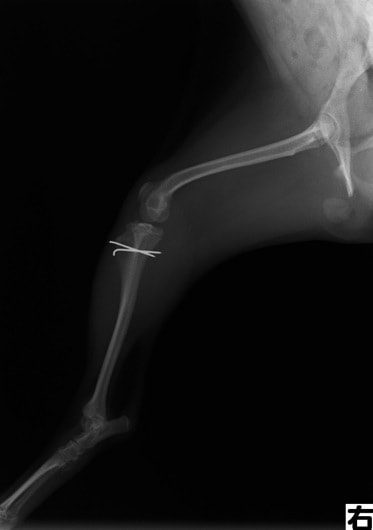

■ 症例20 ポメラニアン 8ヶ月 1.8kg

左右膝蓋骨脱臼 グレードⅢ

2ヶ月前から間欠的跛行が認められ、両膝の膝蓋骨脱臼整復術を行った。

手技は縫工筋及び内側広筋の解放、脛骨粗面の外側転位、滑車ブロック形造溝術、内外側関節包の縫縮を選択し実施した。

右側の膝蓋骨脱臼は上記手技で整復されたものの、左側はそれのみでは膝蓋骨が浮く様子が認められた。その為、PDS縫合糸にて膝蓋靱帯を1糸のみ縫合し、靱帯の縫縮を行った。

膝蓋骨脱臼は膝関節における膝蓋骨の内外側の脱臼と定義されるが、時として単純な内外の脱臼ではなく、膝蓋骨が大きく前方に浮き上がるように脱臼する場合がある。特にトイプードルやポメラニアンといった犬種に多く認められる。

内側脱臼に加えて前方への浮き上がりを矯正する為に、従来より脛骨粗面転移により膝蓋靭帯を外方と下方に引っ張り、固定する方法を選択する。膝蓋骨の前方への浮き上がりが軽度の場合は、従来法ではなく関節包の縫縮で対応していた。しかし、一部の症例で膝蓋骨の動きが悪くなり伸展機構が円滑に機能せずロボット様歩行になるケースがあった。

その為、膝蓋靭帯自体を縫縮する方法を採用した。この方法により、膝関節の伸展機構を妨げず膝蓋骨の軽度の浮きを矯正することが可能となった。

本症例の経過は良好である